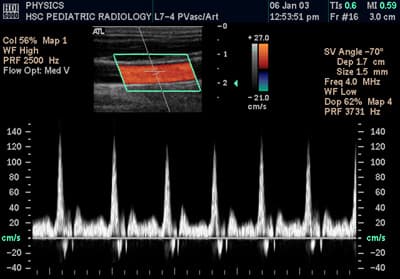

L'échographie Doppler est un examen médical échographique en deux dimensions non invasif qui permet d'explorer les flux sanguins intracardiaques et intravasculaires. Elle est basée sur un phénomène physique des ultrasons : l'effet Doppler. Elle est souvent surnommée écho Doppler. L'effet Doppler permet de quantifier les vitesses circulatoires. L'échographie permet de visualiser les structures vasculaires. En pratique médicale l'échographie Doppler est utilisée pour explorer le réseau artériel et le réseau veineux afin d'évaluer certaines affections : thrombose veineuse profonde (phlébite), varices, artériopathie, thromboses, anévrismes Au cours des dernières années 1940, le au Naval Medical Institute (Bethesda, Maryland, États-Unis) applique pour la première fois des ultrasons au corps humain à but médical. Puis John Wild utilise les ultrasons en 1949 pour estimer l'épaisseur des tissus intestinaux. Après cette étape fondamentale, il a été qualifié de « père des ultrasons médicaux ». L'ultrasonographie médicale est ensuite utilisée à l'université de Lund en Suède par le cardiologue Inge Edler et par Carl Hellmuth Hertz, fils du physicien Prix Nobel Gustav Ludwig Hertz. Hertz connaissait déjà l'utilisation des ultrasons pour l'examen non destructif des matériaux à l'aide d'un réflectoscope. C'est le que l'équipe Edler-Hertz réussit la première mesure de l'activité cardiaque grâce aux ultrasons. Le de la même année, cette méthode leur permet de réaliser un écho-encéphalogramme. Les développements de cette technique par l'équipe du professeur Ian Donald en Écosse à la maternité de l'hôpital royal de Glasgow conduisent aux premières applications en diagnostic. Ces travaux aboutissent à une publication dans The Lancet le , sous le titre « Investigation of Abdominal Masses by Pulsed Ultrasound ». L'année suivante, le physicien japonais Shigeo Satomura est à l'origine d'une version commerciale d'un appareil de mesure des pulsations des vaisseaux sanguins par effet Doppler, le Doppler Rheograph de la société NEC.